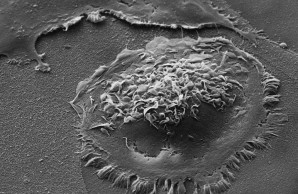

The section Translation & Histology is mainly concerned with the comprehensive histological analysis of bone and bone-associated cells. The focus lies on the translation of mechanical to biological signals, the patho-mechanisms of genetic disorders of the musculoskeletal system and the implant/biomaterial interface with bone.

Pathological alterations in the structural integrity and elemental composition of the bone matrix impact fracture resistance significantly and thereby affect the patients health status. The aim of the Heisenberg Research Group is to decipher the underlying mechanisms at each level of bone’s complex hierarchical structure using a multiscale, integrated approach combining osseous cell imaging with bone quality assessment and medical imaging techniques.

The section Deep Phenotyping & Histomorphometry is focused on the detailed and in-depth analysis of osteological in vivo and in vitro models. These investigations give raise to comprehensive knowledge that allows drawing conclusions on basic process in skeletal biology and pathomechanisms of specific musculoskeletal disorders.

Through the application of a combination of innovative and classical methods of osteological research, we are able to address even the most challenging scientific questions. A special focus is on histomorphometry, the structural and cellular measurement of osteological sections.